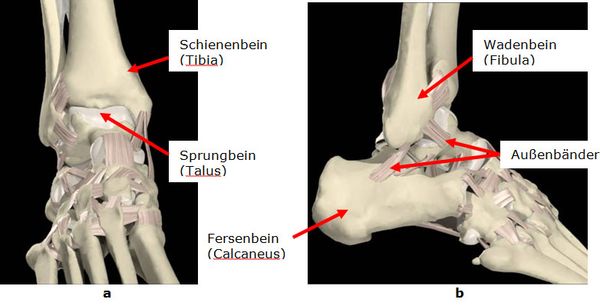

Das obere Sprunggelenk ist ein Scharniergelenk. Die beiden Unterschenkelknochen (Wadenbein, Schienenbein) bilden eine Gabel in der sich das Sprungbein als Rolle bewegt. Zur Sicherung der freien Beweglichkeit ist die Gelenkkapsel vorne und hinten weit und dünn. Die Stabilisierung erfolgt über den Innen-, und Außenbandkomplex sowie mehrere große Sehnen. Das Deltaband zieht vom Schienenbein zu mehreren Fußknochen. Der äußere Bandapparat besteht aus drei Bändern die von der Wadenbeinspitze bis zum Sprung- und Fersenbein ziehen.

Abb.1: a Oberes Sprunggelenk von vorne. b und von der Außenseite.